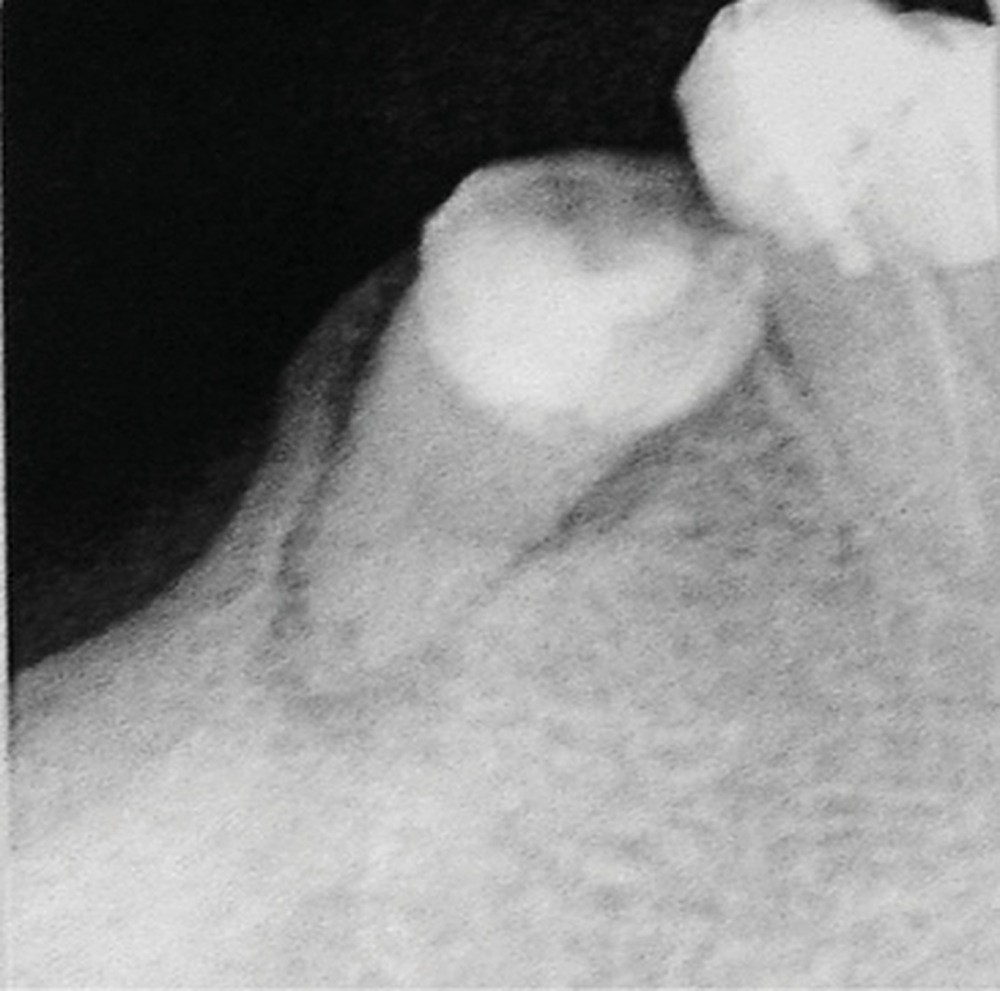

Contexte malin

Un examen clinique attentif prenant en compte les facteurs de risques carieux et parodontaux (contrôle de plaque, tabagisme en particulier) sera réalisé. Un bilan radiographique de première intention sera également nécessaire. A minima, la radio panoramique est indispensable. Elle sera complétée éventuellement par des clichés rétro-alvéolaires. En cas de doute, sur un foyer infectieux chronique péri-apical notamment, ces examens devront être complétés par un bilan d’imagerie tridimensionnel de type scanner ou CBCT. Les lésions de ce type, dans les régions sous-sinusiennes en particulier, sont difficiles d’accès à l’imagerie standard (fig. 1).